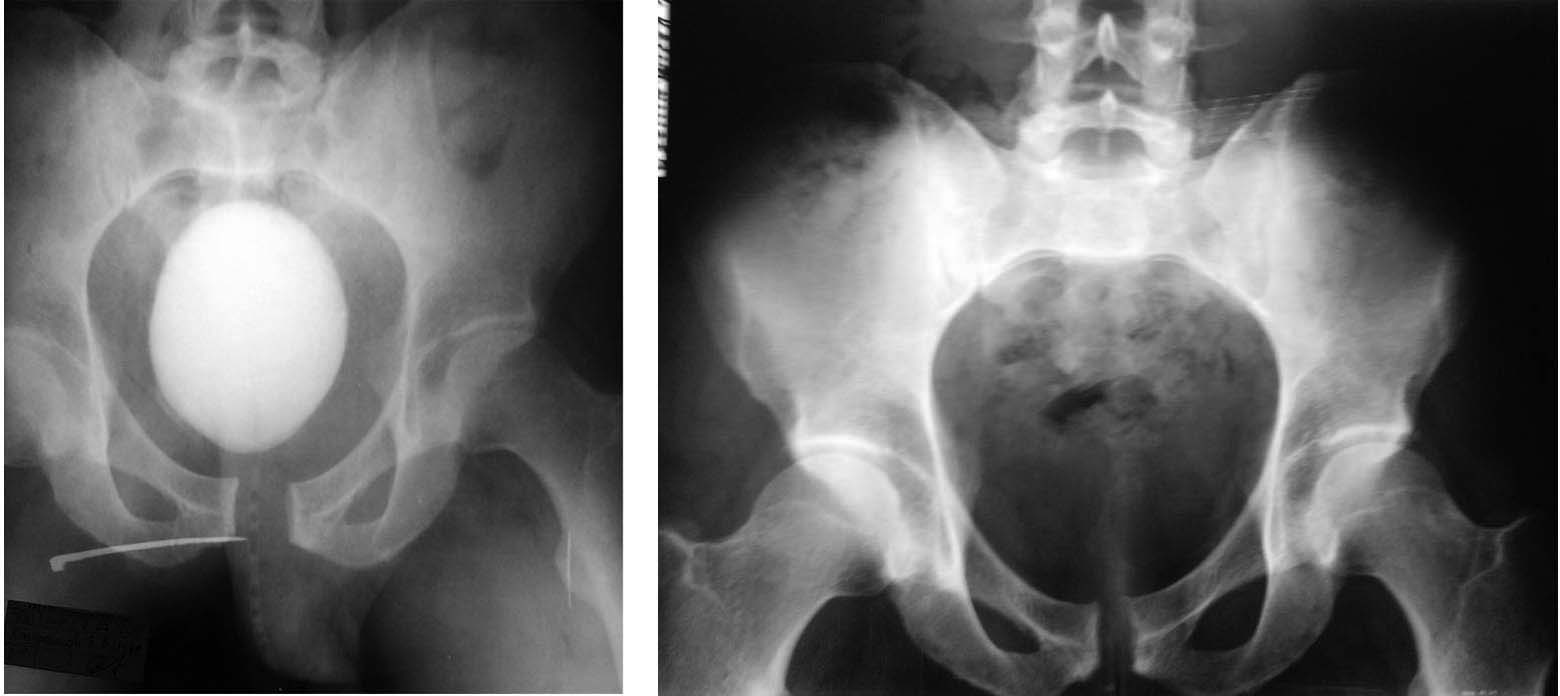

Уронил на себя камень (как говорят альпинисты, «вытащил чемодан»), получил ротационно-нестабильное повреждение таза – разрыв лонного и частично левого крестцово-подвздошного сочленения, внебрюшинный разрыв мочевого пузыря. Лечился в районной больнице (ближайшей к месту получения травмы) – цистостомия, повреждение таза лечилось консервативно (сначала находился в гамаке), примерно с 4 недели начал активизироваться. В настоящее время ходит без средств опоры, испытывает боли в области левого крестцово-подвздошного сочленения при нагрузке (при нагрузке под рюкзаком, например; без нагрузки, т.е. в обычной жизни, чувствует себя неплохо, болей практически нет), в августе мы вместе с ним прошли альпсборы в горах Киргизии, в общем-то восхождения 2-5 категории он выполнял, но видно, что нелегко, походка изменена (что-то наподобие утиной), сам он отмечает улучшение с тех пор как он начал вставать после травмы, клинически определяется ротационная подвижность левой половины таза в пределах 1-1.5 см, пока не может заниматься своей профессиональной деятельностью (промышленный альпинист), так как не может сидеть в беседке. Цистостома полностью зажила.

1. Показана ли стабилизация таза в данной ситуации, или имеет смысл подождать еще какое-то время?

2. Если показана, то достаточно ли выполнить стабилизацию только лонного сочленения или необходима стабилизация и лонного и КП-сочленения, а также сроки выполнения данной операции?

Po predstavlennim snimkam  ne vidno povrezhdeniya SI joint, skoree transforaminal perelom krestsa. Esli sohranyaetsa rotationnaya nestabilnost - sraschenya ne proizoshlo i tolko perednyaya stabilizatsiya  budet bezuspeshnoi - plastina slomaetsa. Neobhodima kombinirovannaya stabilizatsia zadnego i perednego otdelov. No odnaznachnih vivodov po predstavlennim snimkam nelzya - CT taza neobhodimo.